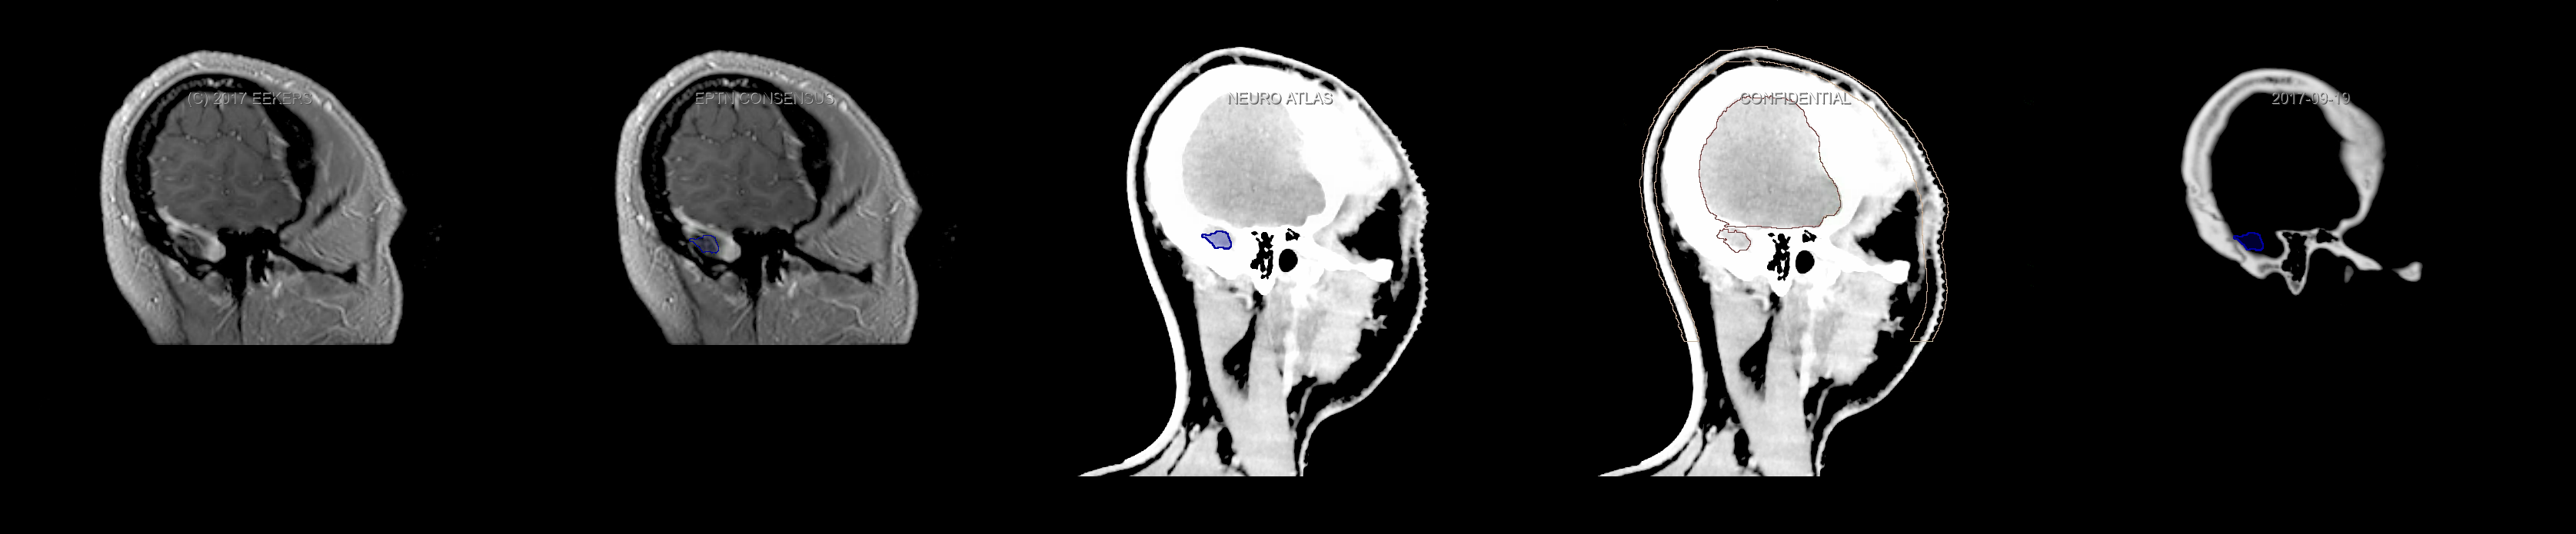

Eekers et al. have published an international neurological atlas for contouring of organs at risk in consensus with the European Particle Therapy Network (EPTN). The purpose of this consensus atlas is to decrease inter- and intra-observer variability in delineating OARs relevant for neuro-oncology. We propose this atlas is used in photon and particle therapy in order to derive consistent dosimetric data. When required this atlas will be updated according to new insights.

Included are all OARs known to be relevant for radiation-induced toxicity in neuro-oncology: brain, brainstem, cochlea, vestibulum & semicircular canals, cornea, lens, retina, lacrimal gland, optic nerve, chiasm, pituitary, hippocampus and skin. A new OAR relevant for neuro-cognition, the posterior cerebellum is also included.

Three-dimensional delineation of the fifteen consensus OARs for neuro-oncology are shown on CT and 3 Tesla (3T) MR images (slice thickness 1 mm with intravenous contrast agent). All are presented in transversal, sagittal and coronal view.

From left to right: MR without structures, MR with structures, CT (WW/WL 120/40) with structures, CT (WW/WL 120/40) with Brain and Brainstem Surface, CT (WW/WL 1500/120)with structures